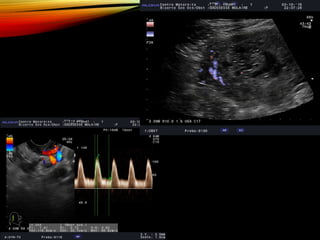

ECHOGRAPHIE

• #16 MASSE INTRACAVITAIRE CONTENANT DE NOMBREUX MICROKYSTES SANS IMAGE EMBRYONNAIRE ET SANS INVASION DU MYOMETRE (PAS DE DOPPLER DANS LA MASSE) +/- ASPECT D’OVAIRES MULTIFOLLICULAIRES (+/ HEMORRAGIQUES)

• #17 Interet doppler 3D

• #29 Blood flow velocity waveformindex refers to any index calculated froma Doppler shift spectrum like pulsatility index (PI), resistance index (RI), and systolic diastolic ratio (S :D ratio).Moreover, through the 3D vascular indices, that is, vascularization index (VI), flow index (FI), and vascularization-flow index (VFI) by using virtual organ computer-aided analysis (VOCAL)